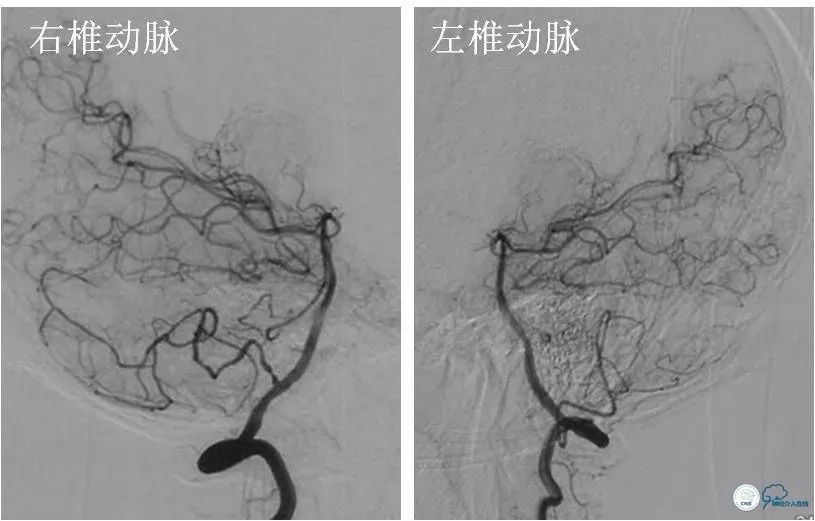

DSA(2018-6-1):右颈内动脉C7段重度狭窄,右颈内动脉系孤立颈动脉系统,右大脑前动脉A1段发育不良或者缺如。前交通动脉开放,见右大脑前动脉经软脑膜动脉向右大脑中动脉供血区域代偿。未见明显后循环参与代偿(图3-5)。

图3

图4

图5